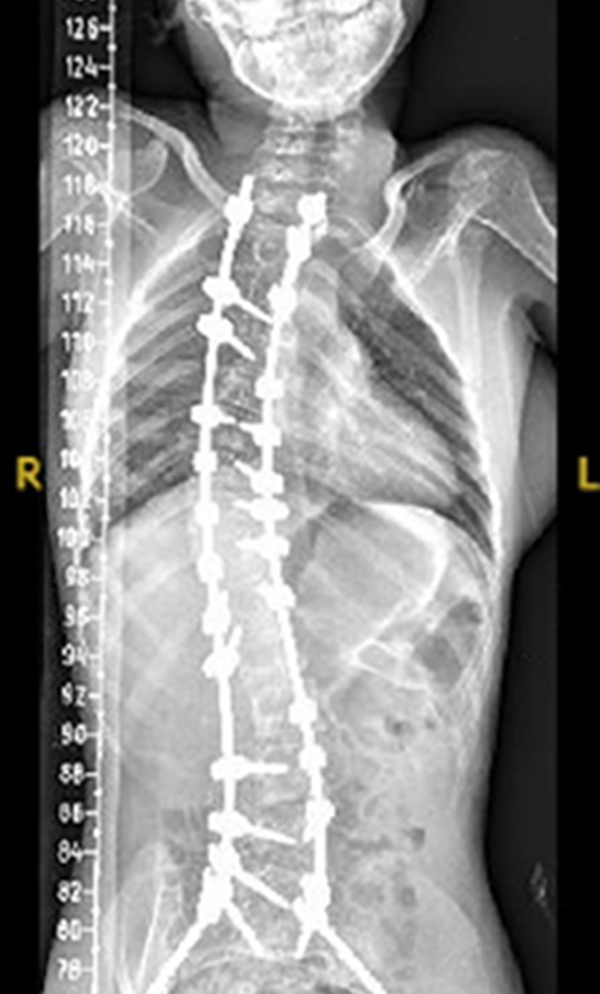

Gallery : Before - After